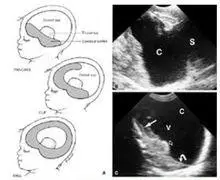

无叶型全前脑:脑中线消失,丘脑完全融合, 半叶型全前脑:脑中线部分

实战叶状全前脑和中线变异型全前脑鉴别

全前脑畸形

无叶型前脑无裂畸形(简称无叶全前脑),严重脑膜脑膨出等9种(2022年版